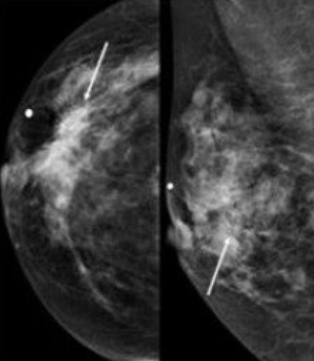

⚠️ 즉시 병원 가야 할 신호

- 돌덩이처럼 딱딱한 멍울(움직이지 않음)

- 유두에서 자국 없는 혈액 분비

- 피부가 오렌지 껍질처럼 울퉁불퉁

- 2주 이상 지속되는 겨드랑이 통증

- 40대~: 매년 유방촬영술(mammography)